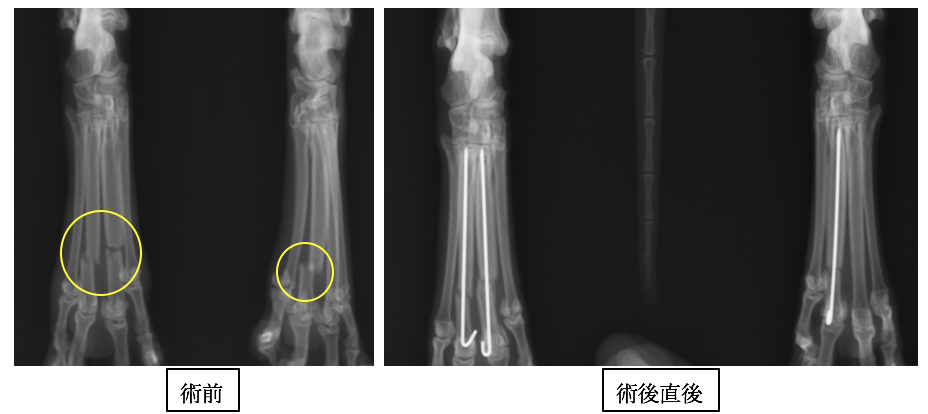

中野区 練馬区 江古田の森ペットクリニックの症例紹介 一般外科症例をご紹介しております